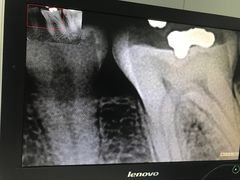

• 武汉大学人民医院(首义院区)

• -武汉大学人民医院(首义院区)

洲之珍珠快入锅 | 18-06-22

黎子_1831 | 18-06-17

请叫我官人 | 18-05-28

Q糯米糍 | 18-05-10

Q糯米糍 | 18-04-26

Q糯米糍 | 18-04-25